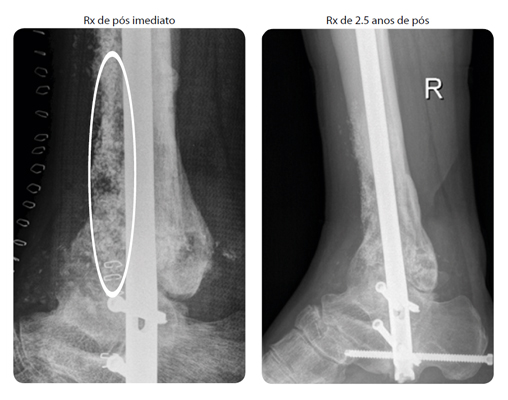

Paciente: Homem de 36 anos com osteomielite crônica em tíbia distal. Após o debridamento cirúrgico, o tamanho do defeito era de 100 cc.

Procedimento: O paciente teve uma fratura em pilão num acidente de carro e a fratura foi estabilizada com uma placa anterior na tíbia distal. O paciente foi diagnosticado com severa osteomielite crônica com grande formação de pus na distal da tíbia. A placa de fixação foi removida e a área foi limpa cirurgicamente através de debridamento radical. O defeito foi preenchido com 48 cc de Bon-Alive® granules, de 2.0-3.15mm misturado com a mesma quantidade de osso autólogo.

Evolução Clínica: O tecido mole teve uma boa cicatrização. Entretanto, uma significante parte do córtex anterior da tíbia distal foi removida, houve a formação de novo osso cortical. Após 2 anos e 6 meses de pós operatório, a fusão estava estável e a evolução do paciente continuou a ter sucesso.